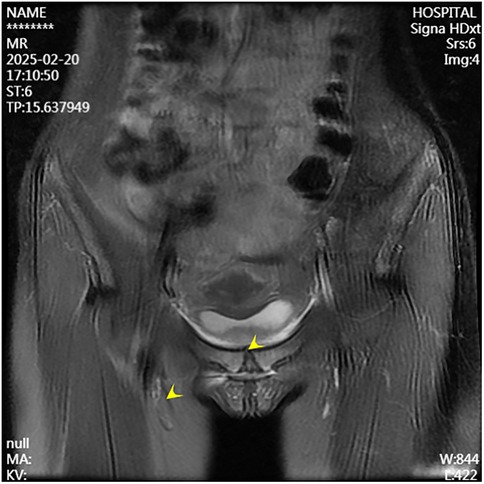

A second surgical procedure was performed four days later. This involved VCS implantation, repeat debridement of the pubic symphysis, and bilateral pubic bone fenestration with drainage. During the procedure, 2 grams of vancomycin powder were combined with 5 milliliters of Stimula® calcium sulfate powder and 2.6 milliliters of sterile water for injection. Following approximately 30 s of thorough mixing, a homogeneous paste was achieved. This paste was subsequently placed into a mold to form hemispherical beads with a diameter of 4.0 millimeters. The antibiotic beads were allowed to set for approximately 15 min before being extracted from the mold for intraoperative application. Under fluoroscopic guidance, the beads were implanted into the medullary cavity. Once the cavity was confirmed to be adequately filled, additional VCS beads were applied to cover the cortical surface of the bone window and the defect area, thereby restoring the structural contour of the local bone. Postoperative serum vancomycin levels were assessed every three days starting from the first postoperative day, with dosage adjustments made based on pharmacokinetic analysis to ensure concentrations remained within the target therapeutic range. Concurrently, routine evaluations of hepatic and renal function, electrolytes (including calcium), and superficial ultrasound examinations of the surgical site were conducted, which revealed no significant fluid accumulation. Laboratory results were within normal limits: white blood cell count at 6.01 × 109/L, neutrophil percentage at 54.3%, C-reactive protein at 2.43 mg/L, procalcitonin levels below 0.1 ng/ml, erythrocyte sedimentation rate at 10 mm/h, negative blood cultures, and normal hepatic and renal function, electrolytes, and calcium levels. The patient had no relevant postoperative symptoms such as frequent urination, urgent urination, hematuria, or dysuria.By one week postoperatively, the surgical incision had healed by primary intention, pain at the pubic symphysis had fully resolved, and lower limb motor function had returned to normal, with full hip abduction and internal rotation. Imaging conducted at two weeks post-surgery revealed the presence of residual antibiotic beads and localized infection with osteolytic defects in the pubic symphysis (Figures 4, 5). Following discharge, the patient underwent a four-week regimen of oral vancomycin aimed at eradicating any residual infection and was advised to refrain from engaging in strenuous activities for three months. Subsequent imaging at the six-week mark revealed complete absorption of the calcium sulfate artificial bone, resolution of prior infectious indicators, and a visible periosteal reaction indicative of active bone remodeling (Figures 6, 7). By the 22-week follow-up, callus formation was evident in the bilateral pubic rami, signifying successful osseous healing (Figure 8).

Figure 4. Follow-up MRI at two weeks postoperatively shows controlled infection at the pubic symphysis.

Figure 6. Follow-up MRI at six weeks postoperatively demonstrates resolved infection at the pubic symphysis.